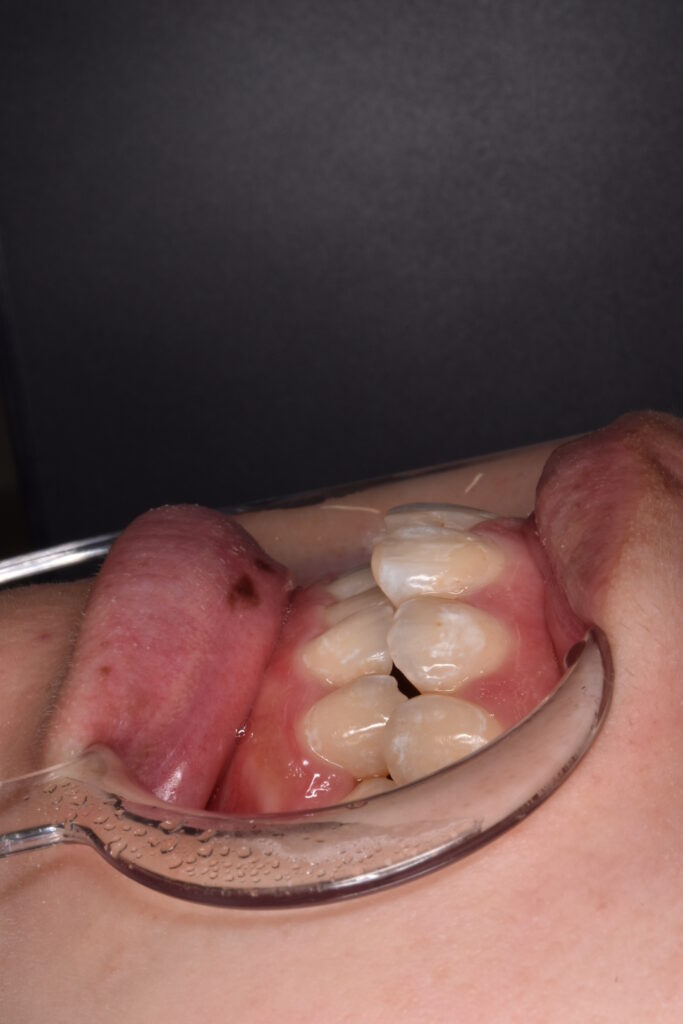

矯正後

矯正はインビザライン モデレートで行っています。追加アライナーなし 途中妊娠出産のため来院間隔が空いています。